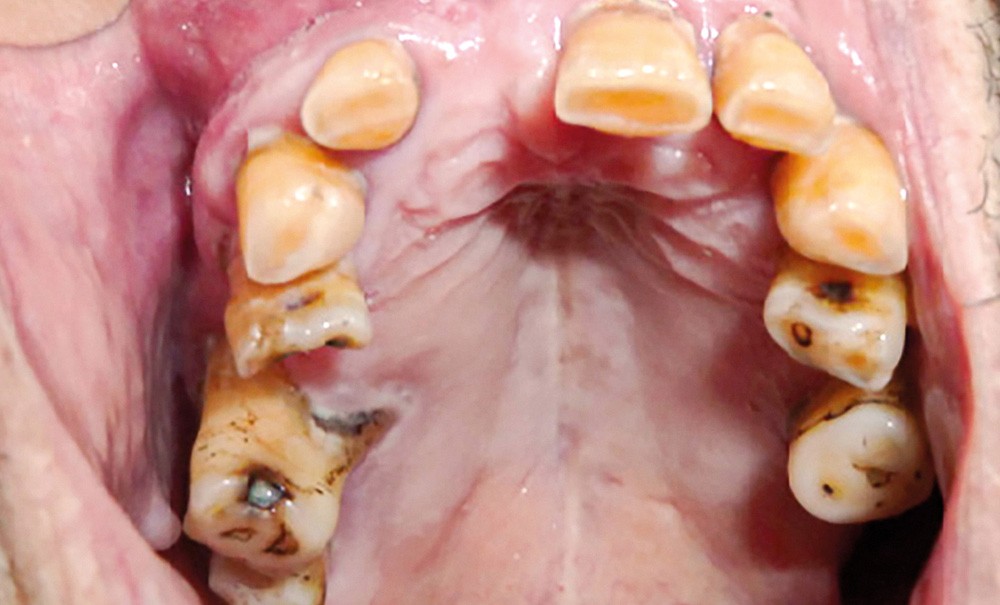

L’examen intra-oral montre un comblement au fond du vestibule au niveau de tout le secteur antérieur depuis l’incisive centrale gauche (21) jusqu’à la première prémolaire droite (14), la muqueuse est d’aspect sain (fig. 4). La palpation vestibulaire haute révèle une masse élastique sous-muqueuse située au niveau du plancher nasal antérieur, dépressible et légèrement douloureuse.

L’origine dentaire a été écartée par la clinique (aucun antécédent de douleurs dentaires et le test de vitalité pulpaire est positif sur les dents antérieures) et par l’orthopantomogramme, qui n’a révélé aucune modification des structures osseuses.